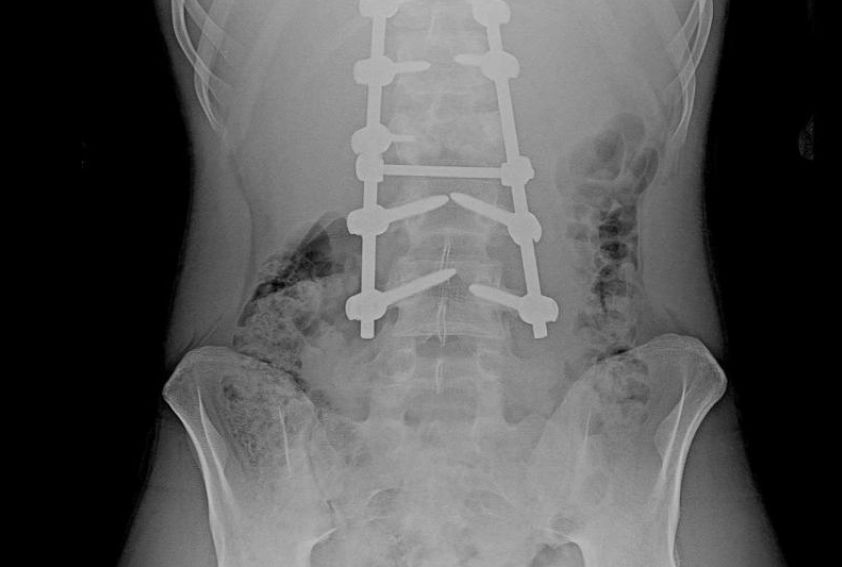

Восстановление после тяжелой травмы: воронежские врачи вернули молодому человеку способность ходить

16-летний парень, получивший тяжелую травму на стройке, полностью восстановился благодаря усилиям врачей в Воронеже. История восстановления стала примером профессионализма и эффективности лечения.

Воронежский подросток вернулся к активной жизни после сложного лечения позвоночника

Воронежский подросток после тяжелой травмы вернулся к полноценной жизни благодаря сложной операции и реабилитации.